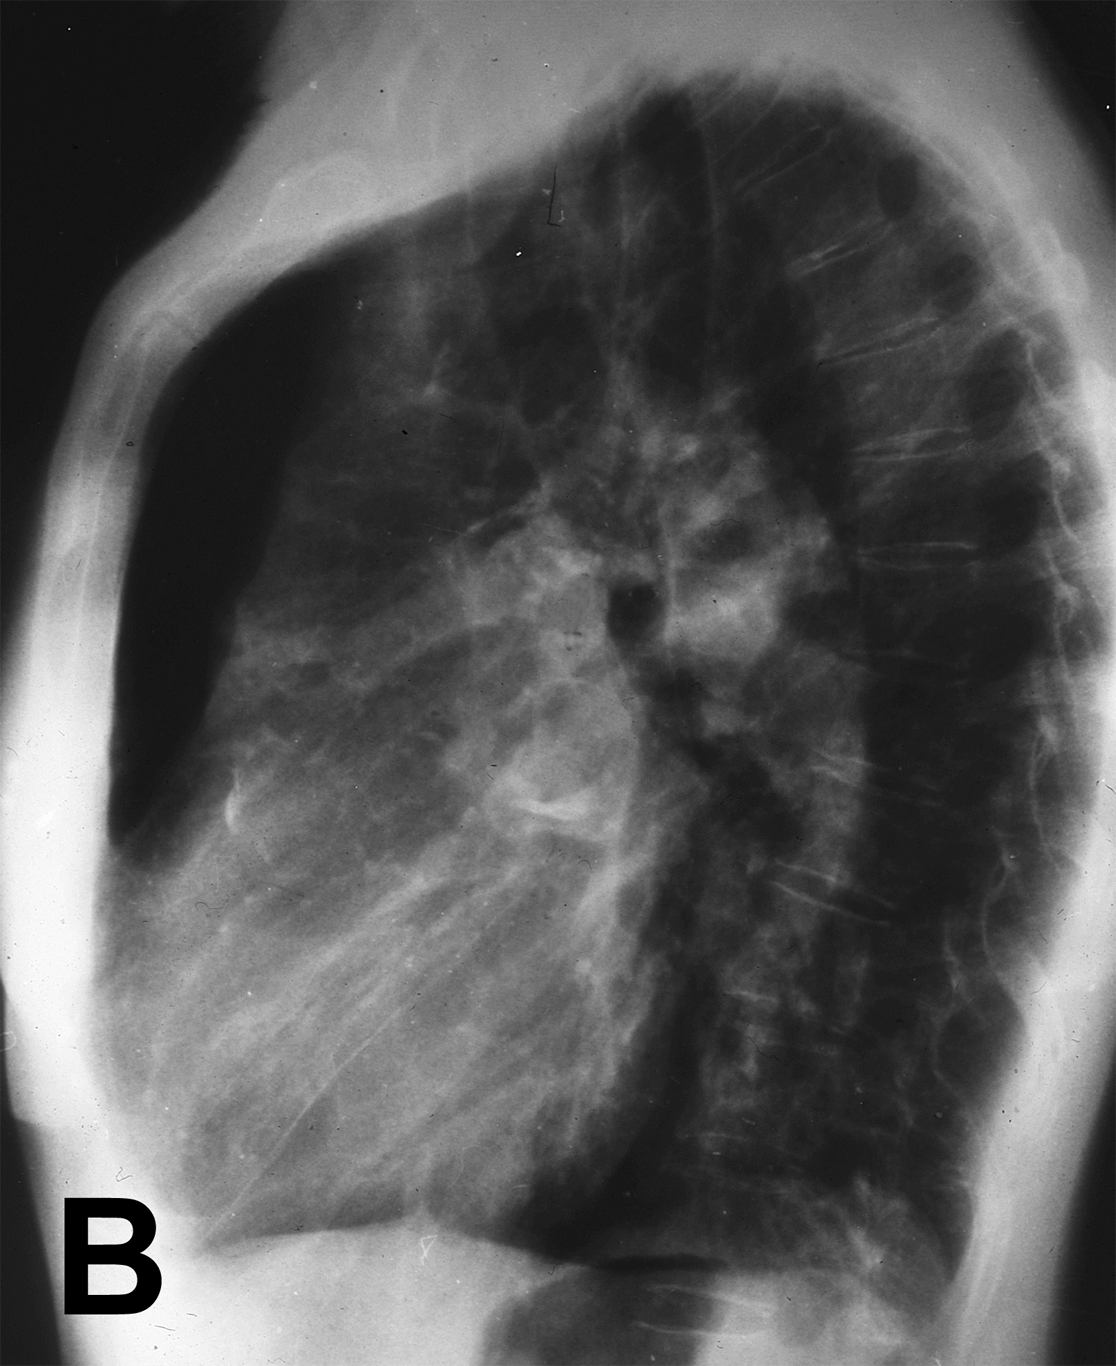

Chest X-ray showed significantly dilated pulmonary vessels and a round calcified mass in the left pulmonary hilum (Figures 1A, 1B). The patient died suddenly on the following day. Autopsy revealed a large (28 mm) communication between the pulmonary trunk and the aorta (Figure 2).

Figure 1: A) Chest radiograph demonstrating dilated pulmonary vessels and, B) round calcified mass in the left pulmonary hilum.